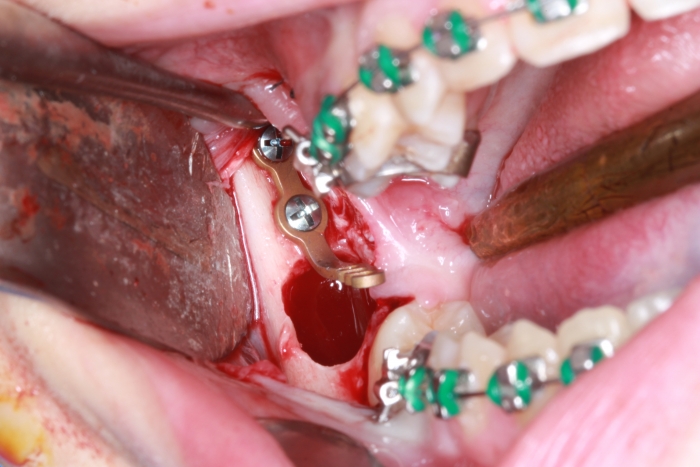

Extração dos 4 terceiros molares   - Instalação de placas de ancoragem - Clínica Cliniface

Extração dos 4 terceiros molares - Instalação de placas de ancoragem